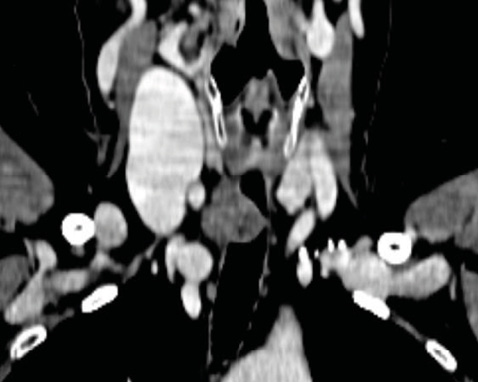

Пацієнтка віком 67 років була госпіталізована з клінічними проявами вираженої дихальної недостатності. Захворювання дебютувало гостро з прогресуючою задишкою. У районній лікарні виконано комп’ютерну томографію шиї та органів грудної клітки, за даними якої виявлено об’ємне новоутворення у верхній третині трахеї (рис. 1).

Рис. 1. Дані комп’ютерної томографії